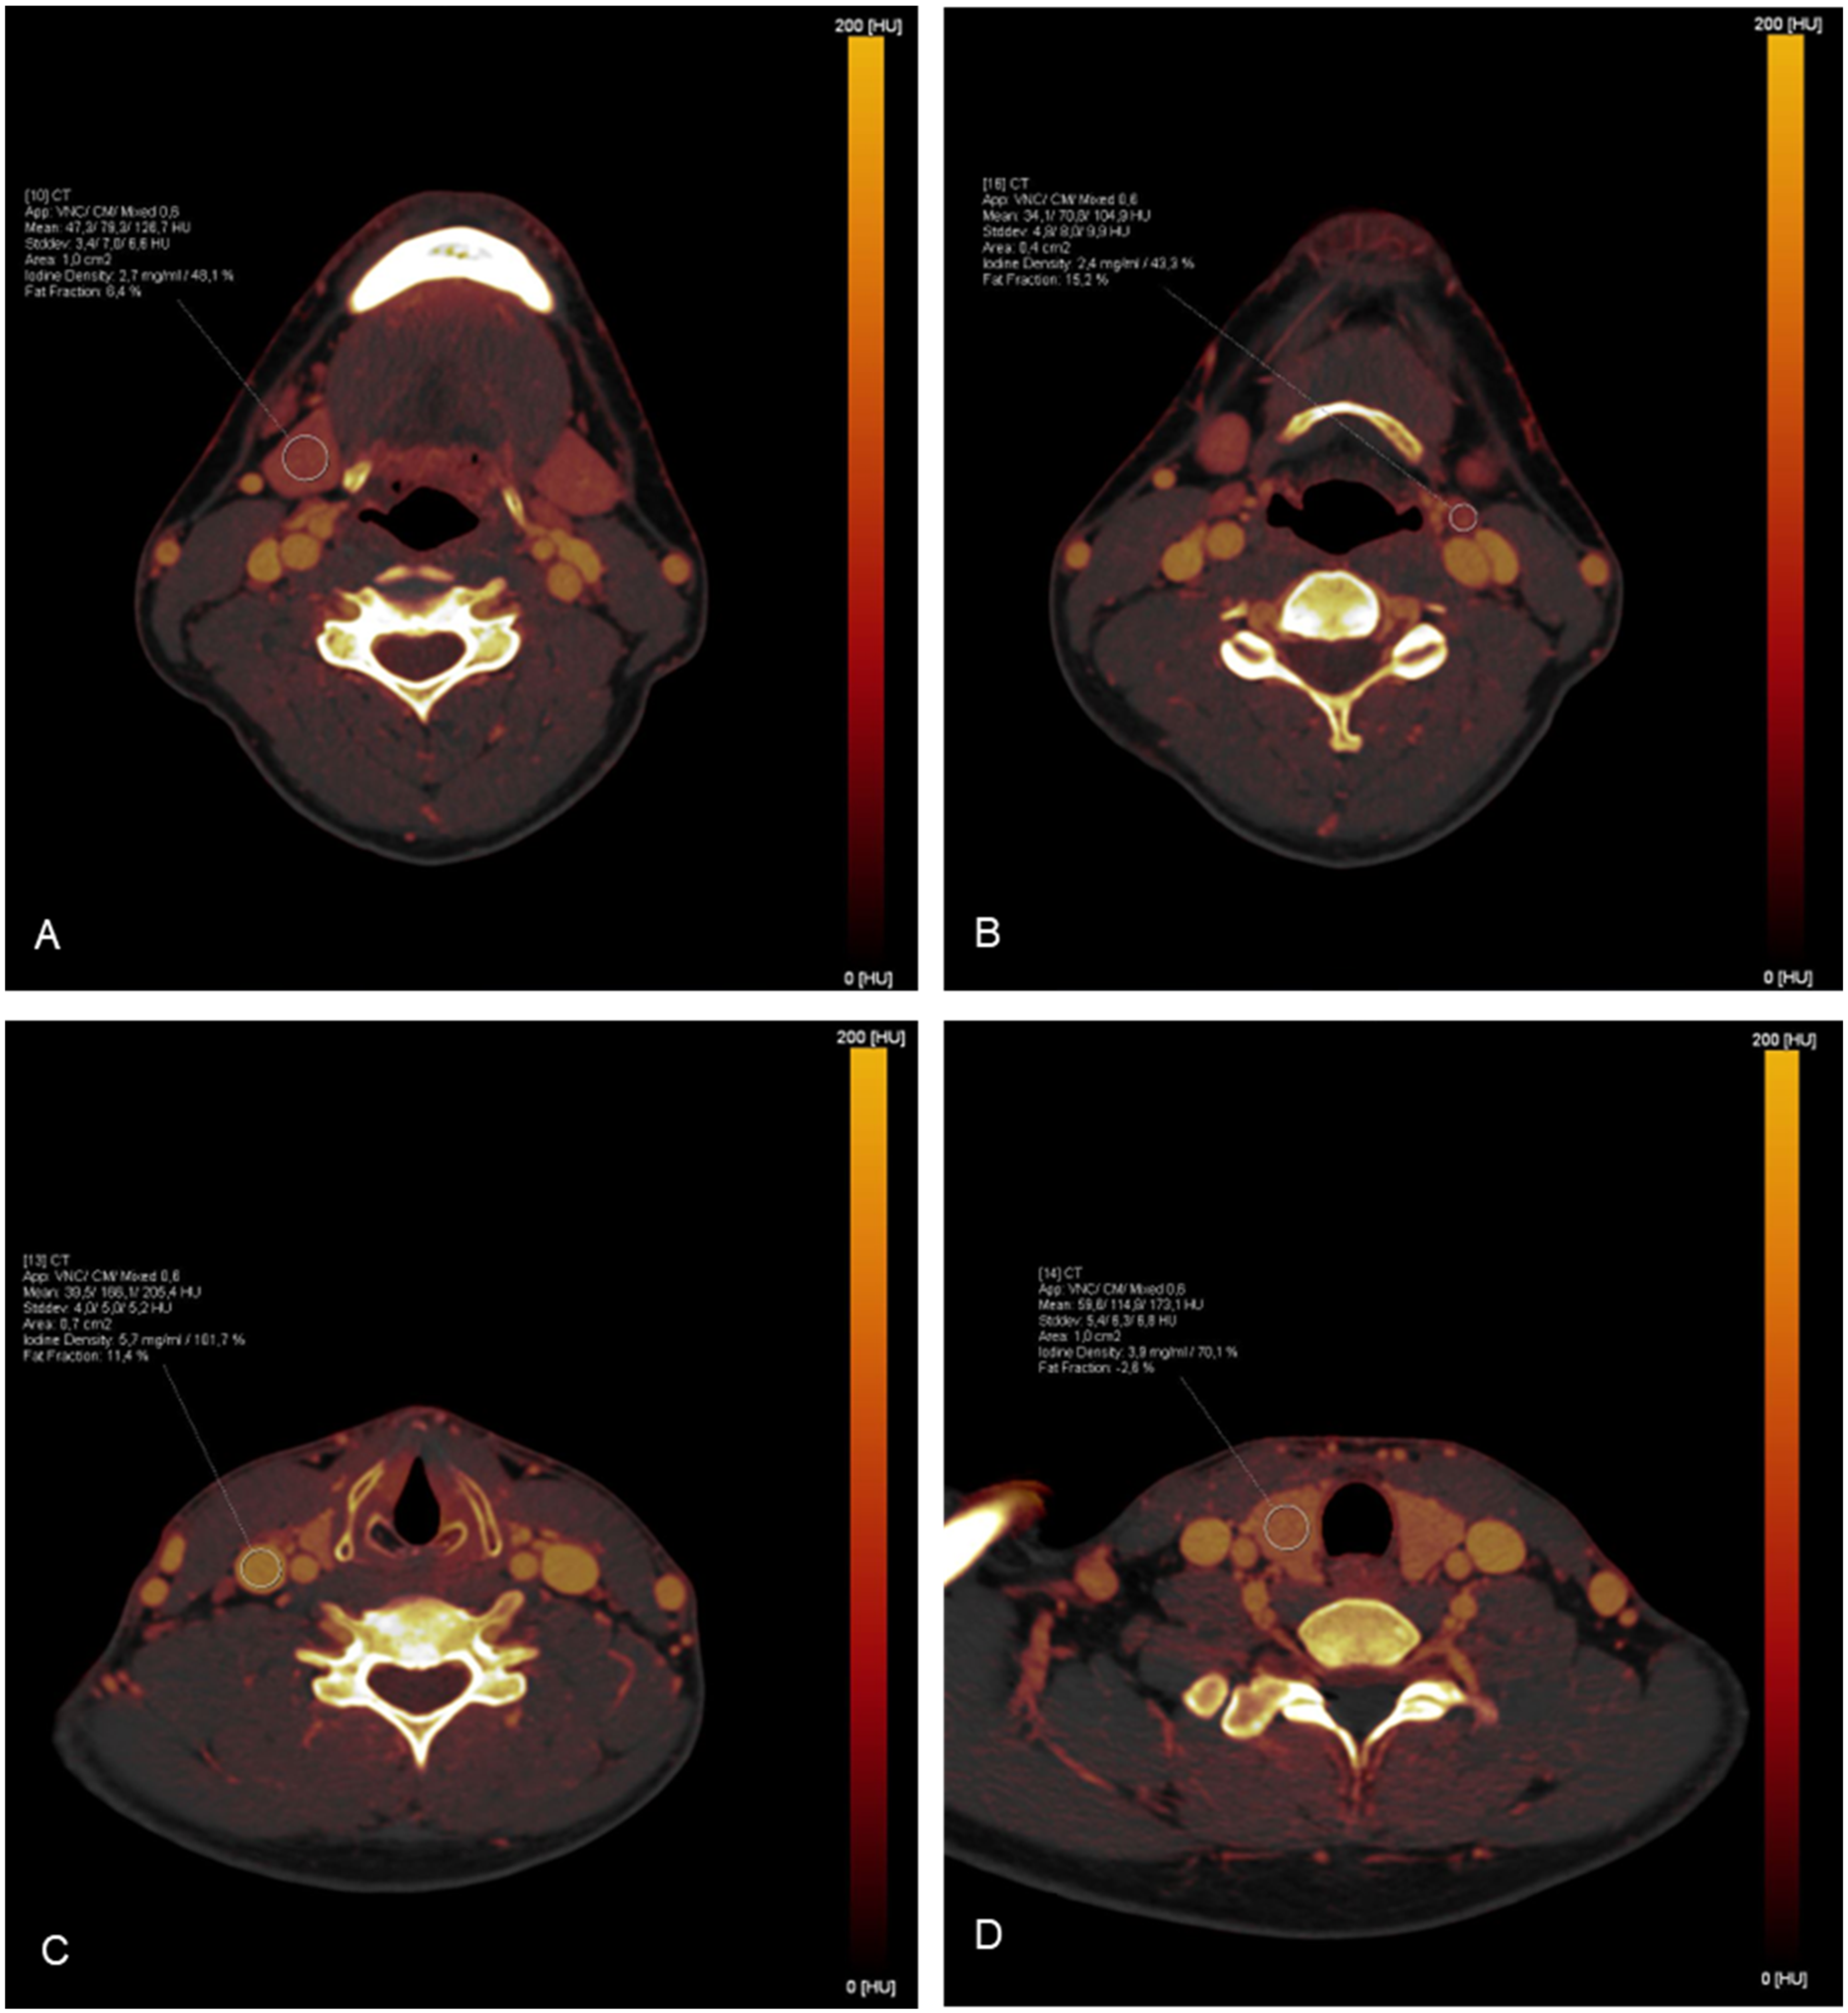

2.3. Iodine Mapping and Uptake Measurements

| Structure | Number of ROI | ROI Placement |

|---|---|---|

| Carotid artery | 2 | central within the vessel at the level of the thyroid gland |

| Jugular vein | 2 | central within the vessel at the level of the thyroid gland |

| Temporal lobe | 2 | right and left temporal lobe |

| Cerebellum | 2 | right and left cerebellum |

| Parotid glands | 2 | right and left gland, avoiding duct |

| Masseter muscle | 2 | the superficial portion on both sides |

| Uvula | 1 | distal of the soft palatine |

| Submandibular glands | 2 | right and left gland, avoiding duct |

| Sublingual glands | 2 | right and left gland, avoiding surrounding tissue |

| Palatine tonsils | 2 | at the most prominent portion |

| Tongue | 2 | right and left half of the tongue |

| Lingual tonsil | 1 | at the most prominent portion |

| Vocal cords | 2 | at the level of arytenoid cartilage |

| Thyroid gland | 4 | upper and lower portion, both sides |

| Cervical lymph nodes | 5 | one on each cervical lymph node level |

| Sternocleidomastoid muscle | 2 | common muscle belly |